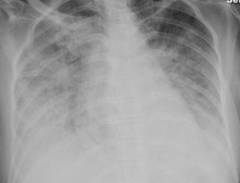

- Рентгенография грудной клетки выявляет признаки жидкости в легких.

- Рентгенография грудной клетки выявляет наличие жидкости в легочной паренхиме. На снимках видно однородное затемнение легочных полей, которое может быть симметричным или асимметричным. Например, при сердечной недостаточности отёк двусторонний, а при односторонней пневмонии — односторонний.